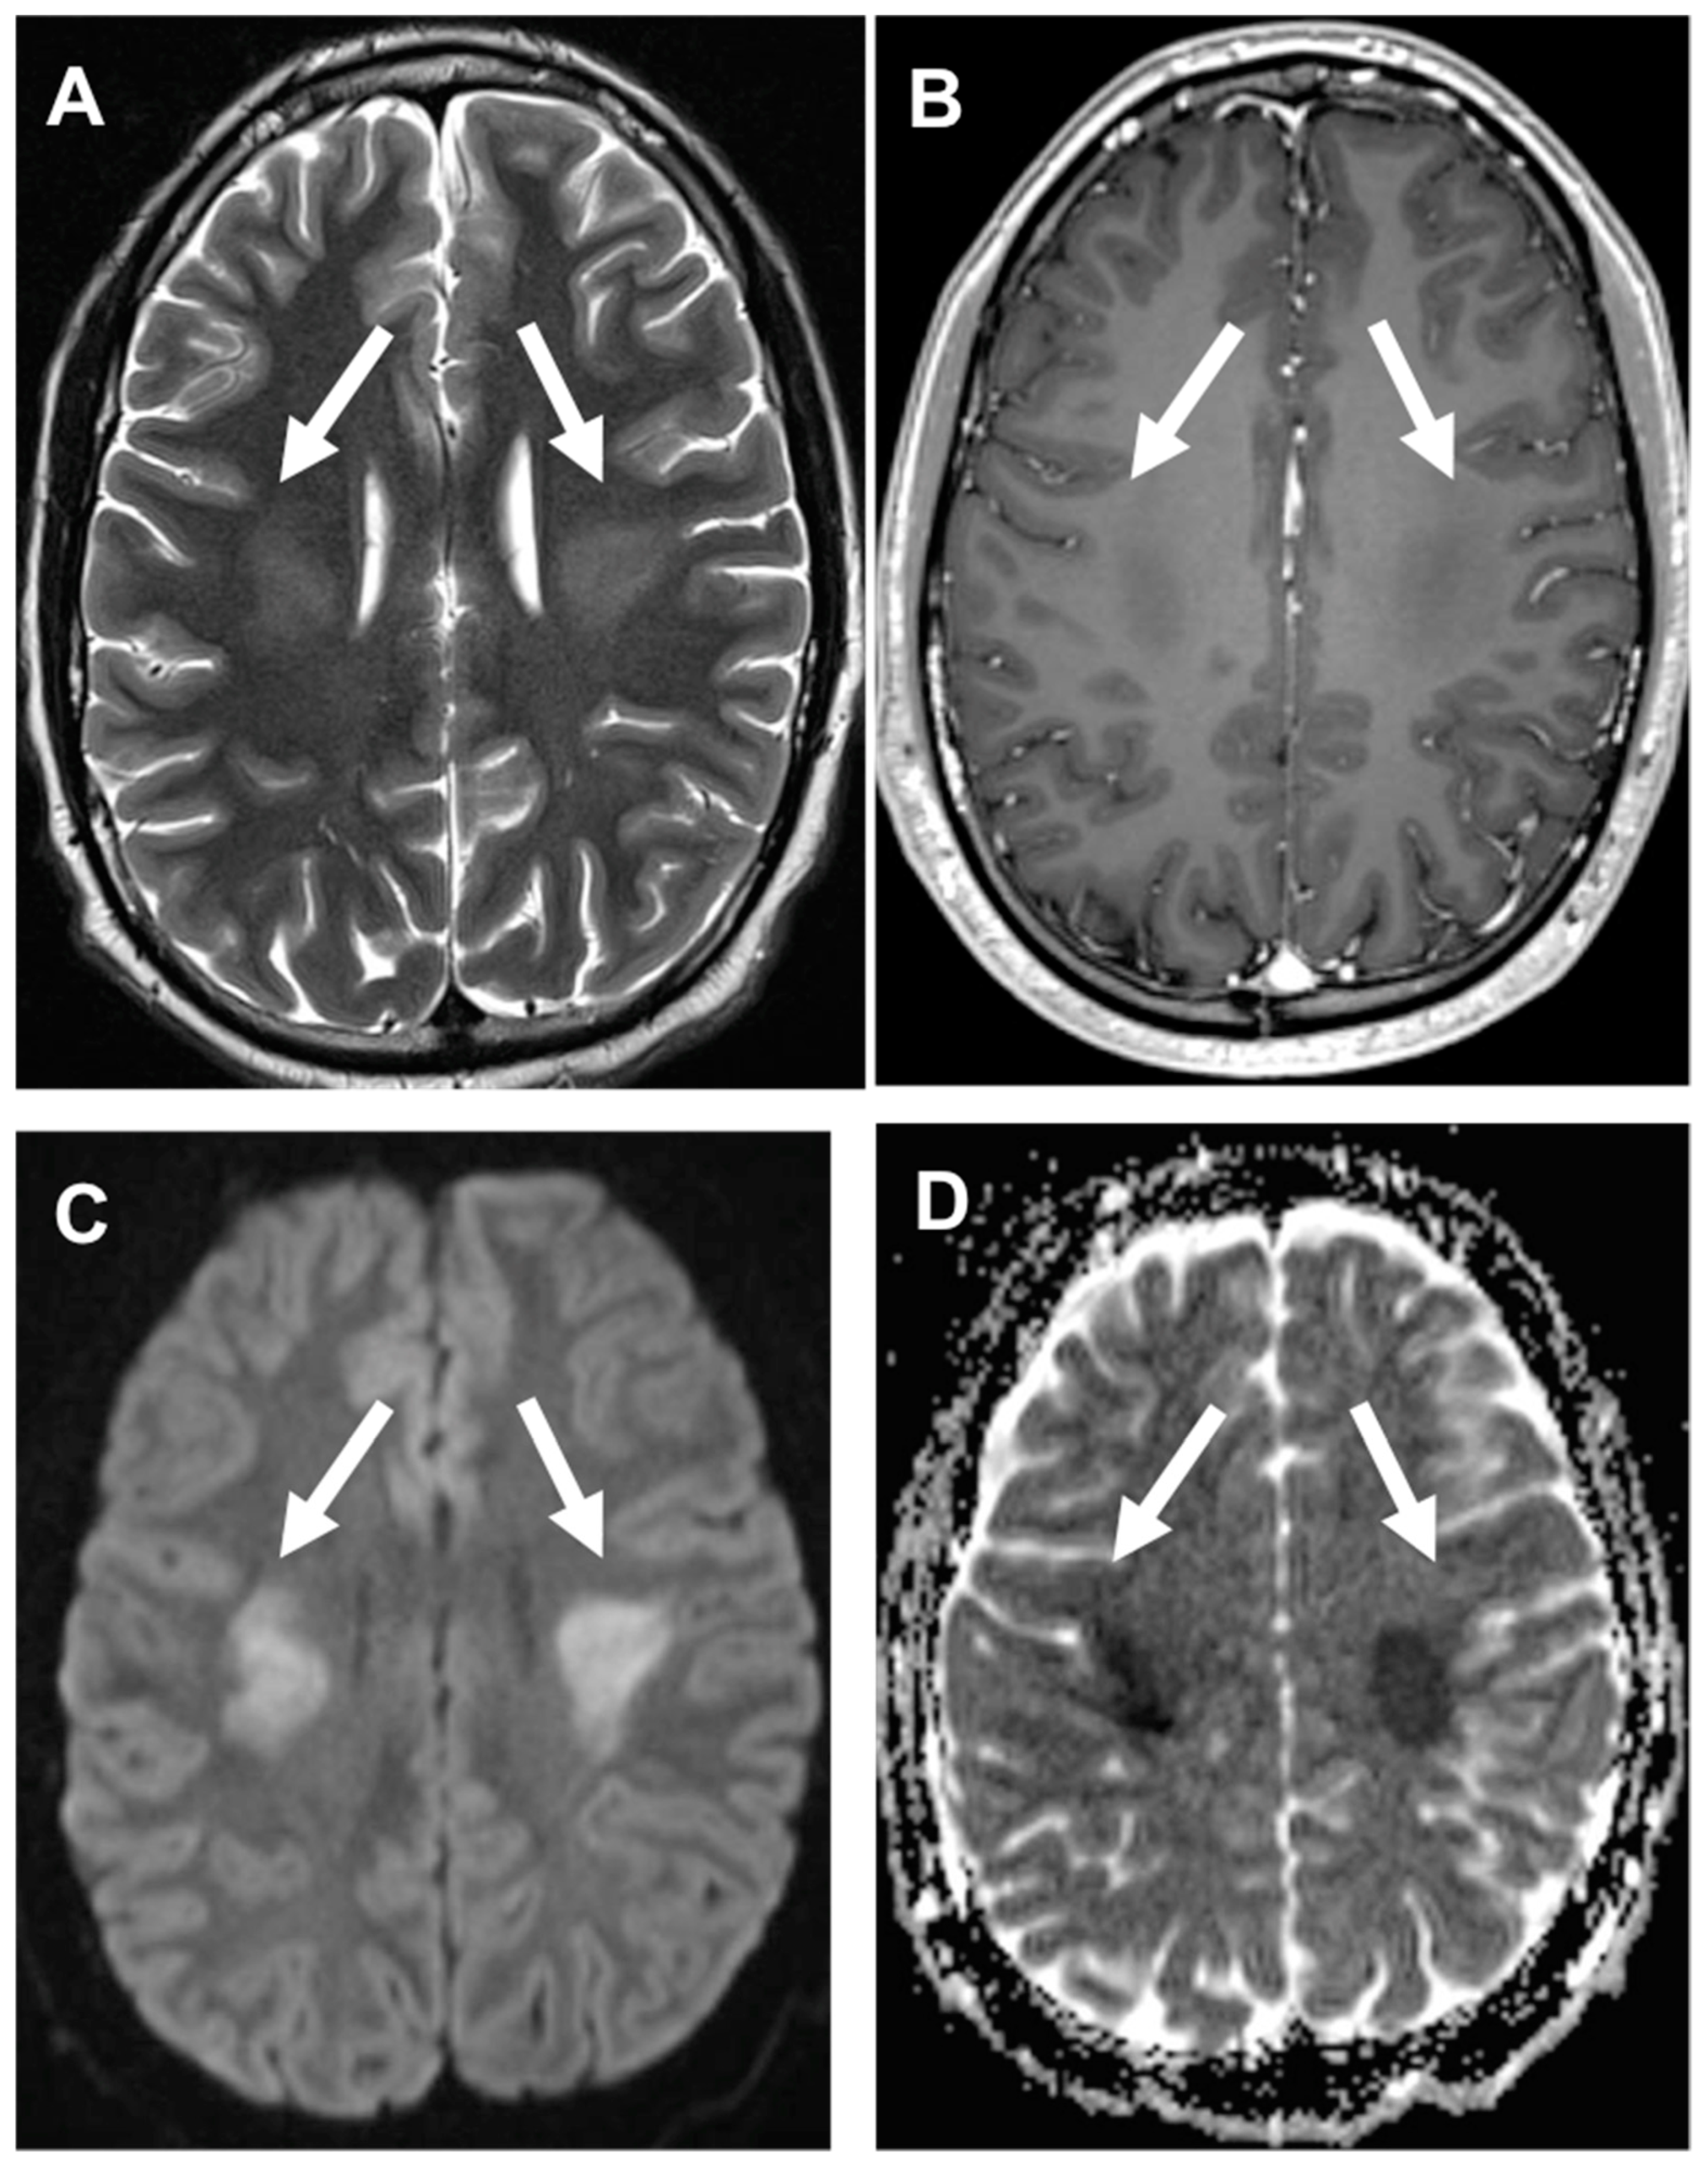

3.3. Stroke-like Migraine Attacks after Radiation Therapy

- Kerklaan, J.P.; Lycklama á Nijeholt, G.J.; Wiggenraad, R.G.J.; Berghuis, B.; Postma, T.J.; Taphoorn, M.J.B. SMART syndrome: A late reversible complication after radiation therapy for brain tumours. J. Neurol. 2011, 258, 1098–1104. [Google Scholar] [CrossRef] [PubMed] [Green Version]

- Rigamonti, A.; Lauria, G.; Mantero, V.; Filizzolo, M.; Salmaggi, A. SMART (stroke-like migraine attack after radiation therapy) syndrome: A case report with review of the literature. Neurol. Sci. 2016, 37, 157–161. [Google Scholar] [CrossRef]

- Armstrong, A.E.; Gillan, E.; Di Mario, F.J. SMART Syndrome (Stroke-Like Migraine Attacks After Radiation Therapy) in Adult and Pediatric Patients. J. Child Neurol. 2014, 29, 336–341. [Google Scholar] [CrossRef]

- Farid, K.; Meissner, W.G.; Samier-Foubert, A.; Barret, O.; Menegon, P.; Rouanet, F.; Fernandez, P.; Orgogozo, J.M.; Allard, M.; Tison, F.; et al. Normal Cerebrovascular Reactivity in Stroke-Like Migraine Attacks After Radiation Therapy Syndrome. Clin. Nucl. Med. 2010, 35, 583–585. [Google Scholar] [CrossRef]

- Black, D.F.; Morris, J.M.; Lindell, E.P.; Krecke, K.N.; Worrell, G.A.; Bartleson, J.D.; Lachance, D.H. Stroke-Like Migraine Attacks after Radiation Therapy (SMART) Syndrome Is Not Always Completely Reversible: A Case Series. Am. J. Neuroradiol. 2013, 34, 2298–2303. [Google Scholar] [CrossRef] [Green Version]